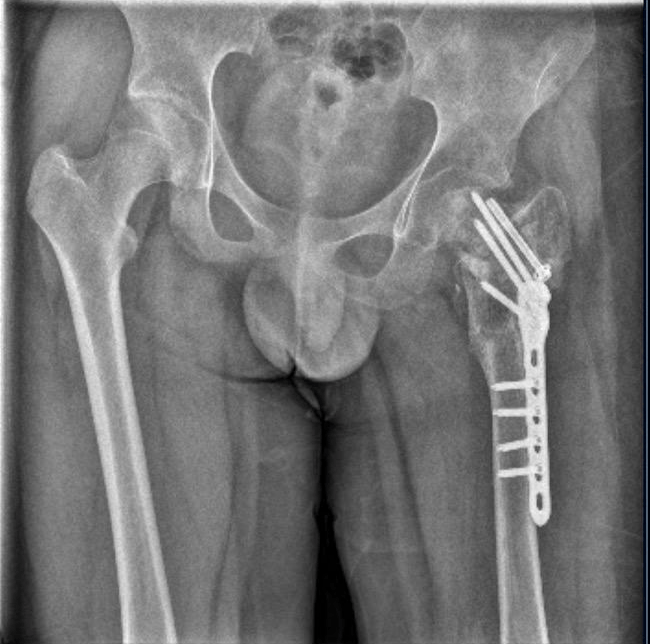

耽误10天,小武错过了最佳治疗时机。9月9日被妈妈送到泉州市正骨医院,他已是陈旧性骨折。医生说,“刚摔时只是骨裂,如果立刻来医院处理,休息一两个月就好了。”

2023年11月13日出院,小武的诊断结论列出左股骨颈陈旧性骨折、左髋部感染、肺部感染等十余种症状。

▲小武左腿骨折

武女士说,事发两年来,小武共做了六次手术,仅左髋部感染就做了四次手术,但损坏部分依然长不出来。如今,小武骨骼萎缩,拄双拐走路时一瘸一拐,成了“长短腿、粗细腿”。

医生说,小武股骨头坏死已到晚期,只能做康复治疗。他的学业也已荒废两年多。医生还说,后期可能要把胯骨和髋骨置换成人工骨骼。但昂贵的医疗费谁来出,至今没有答案。